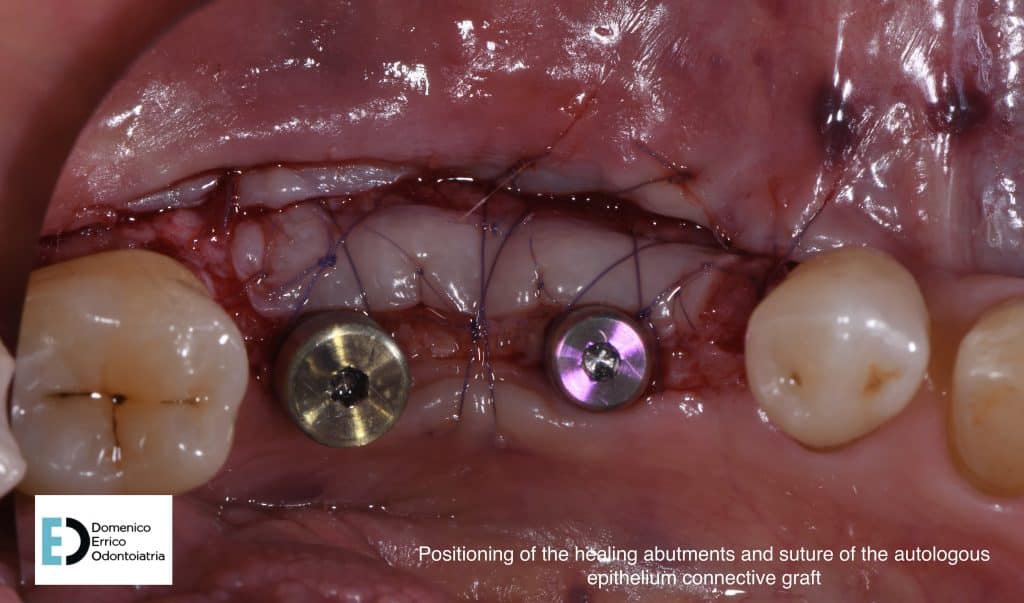

The treatment objectives are primarily functional: the restoration of volumes, necessary for implant rehabilitation due to insufficient bone height for fixture placement applying a mesh with a filler, consisting of 50% autologous bone and 50% heterologous bone; the reinstatement of chewing function by a second intervention to remove the mesh and simultaneously place two implant fixtures, concurrent with an increase of adherent gingival tissue level; and finally, the goal is to achieve the correct vertical relationship between the upper and lower arches through prosthetic rehabilitation of the upper arch with the replacement of the old prosthetic device.

positioning of healing abutments and suture of the autologous epithelium connective graft